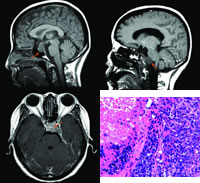

影像学检查 X线胸片正常;肝胆胰脾肾B超正常。垂体MRI +增强:垂体巨腺瘤,双侧视交叉、双侧海绵窦区及左侧颈内动脉海绵窦段均受明显推移(图1、2)。

手术后1周开始给予总剂量50 Gy为期3个月的局部放疗,在放射治疗过程中,患者头痛、复视症状一度缓解,但左眼外展仍受限。放疗开始后2个月,患者头痛再度进行性加重,并出现饮水呛咳及吞咽困难。复查垂体MRI见左侧颞叶内下方,左侧天幕处,左侧斜坡与脑干之间病变(图3)。提示垂体腺癌复发,蛛网膜下腔转移,伴后组颅神经多发损害,提示放疗疗效不佳。

病理报告:垂体腺癌光镜下表现:肿瘤细胞圆形,大小较一致,胞浆少,核大深染,排列成梁状,核分裂多见,血窦丰富伴坏死。(图4)